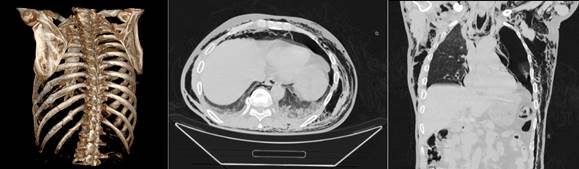

а б в

Рисунок 2. МСКТ. ТОГК.

Мультипланарная 3D-реконструкция: Перелом тела 8 – го ребра слева по средней подмышечной линии без смещения к/о. Переломы 9, 10, 11 -го ребер слева по лопаточной линии со смещениями к/о. Перелом хряща 1 – ребра справа без смещения к/о. Перелом головки 10- го ребра слева без смещения к/о (а), аксиальные срезы в легочном и костном режимах: уплотнение задне-базальных сегментов обеих легких (ушиб легких). Множественные переломы ребер (б, в).